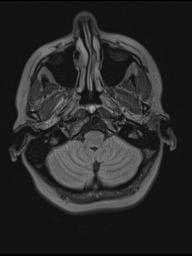

MRI August 2010.

Diagnose: There is no evidence to suspect that this patient may have an active phase of disease.